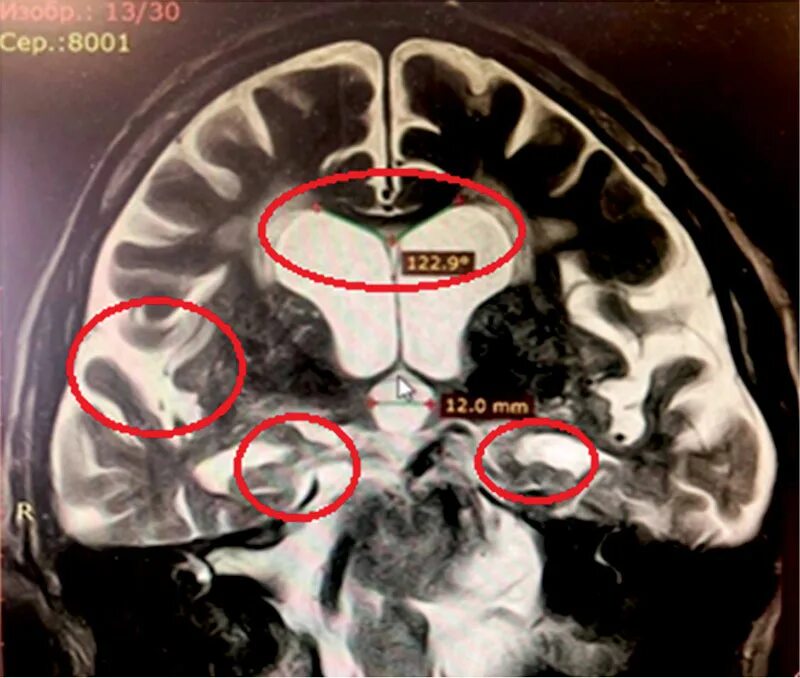

Расширение ликворосодержащих пространств